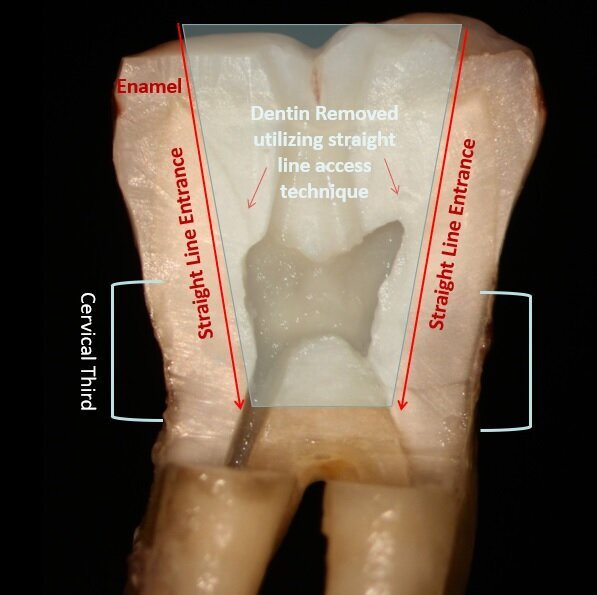

Fig. 2: Traditional endodontic access with an attempt at straight line entrance into the canal orifice typically follows a vertical path necessitating more coronal tooth structure removal.

Fig. 3: An orifice-directed access conserves more tooth structure as it follows the direction of the canal, resulting in a smaller access opening and preservation of critical tooth.

The goal of endodontic access is to locate the canal orifices and allow straight-line access into those canals to permit instrumentation. Traditionally, endodontic access in molars recommended a large access that allowed the files to drop into the canal from a vertical direction essentially parallel to the long axis of that molar. Unfortunately, this approach removes a considerable amount of coronal tooth structure and can weaken the cervical region of the tooth (Fig. 2). Yet anatomically the canals in the molar tend to angle toward the center of the tooth, with the mesial canals tipping to the distal and the distal canals tipping to the mesial. An orifice-directed approach takes this into consideration, and the orifice for the mesial canals has a straight-line access from the distal and the distal canal orifice is approached from the mesial direction (Fig. 3). The goal is preserving critical tooth structure and not potentially weakening the tooth to functional loading following treatment. The Endoguide bur (SS White) is a long shaft friction grip or latch-style bur with a small, pointed head that is designed to aid in location of the orifice and aid in conservative tooth removal laterally to allow access for the file into the canal (Fig. 4). It is recommended that the bur should not be advanced into the canal beyond the length of the bur’s head to prevent potentially perforating the tooth in the cervical region.